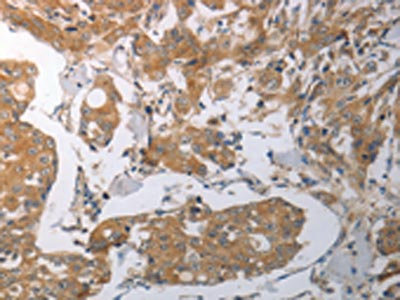

The image on the left is immunohistochemistry of paraffin-embedded Human breast cancer tissue using CSB-PA271756(SHH Antibody) at dilution 1/70, on the right is treated with synthetic peptide. (Original magnification: ×200)

The image on the left is immunohistochemistry of paraffin-embedded Human colon cancer tissue using CSB-PA271756(SHH Antibody) at dilution 1/70, on the right is treated with synthetic peptide. (Original magnification: ×200)